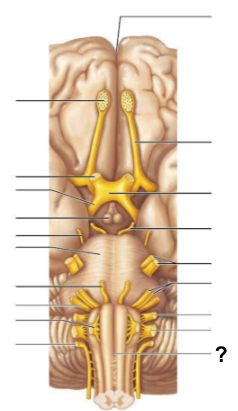

Through which structure, labeled “?”, is CSF absorbed into the venous blood?

Arachnoid villi